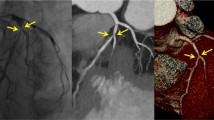

Quantitative image analysis was also performed by the two independent, blinded observers using a window width of 1200 HU and a window level of 240 HU. Patients with non-evaluable stents were excluded in this analysis. Image noise was measured by placing a circular region of interest (ROI) with a diameter of 20 mm in the aortic root, and was defined as its standard deviation (SD). The observers measured attenuation values inside native coronary vessels using the ROI technique (Fig. 2a). Measurements were repeated three times, and the mean values were calculated. In-stent diameters (proximal, middle, distal) were measured using electronic calipers. Attenuation values inside visible stent lumens (proximal, middle, distal) were determined, and mean diameters and values at three different levels were calculated (Fig. 2b, c). These mean diameters and attenuation values were representative of in-stent diameter and attenuation values inside stent lumens. These measurements were performed on the plane perpendicular to the long axis of the vessel using a zoomed field of view. ROIs were drawn as large as possible, while carefully avoiding stent struts and calcifications. To assess the attenuation effects of metallic stent struts on luminal displays, stent lumen attenuation increase ratios (SAIR) were calculated using the following equation: SAIR = (in-stent attenuation-coronary lumen attenuation)/coronary lumen attenuation [14, 15]. A higher value represents the greater blooming effect of metallic stent struts and poorer image quality. To quantify the blooming effects of metallic stent struts, artificial lumen narrowing (ALN) was calculated using the following equation: ANL = (nominal stent diameter-measured lumen diameter)/nominal stent diameter [16]. A higher value represents the greater attenuation effect of metallic stent struts on luminal display and poorer image quality.

A 39-year-old man with a coronary stent in the left anterior descending artery. Curved multiplanar reformatted CT images and transverse sections of the coronary artery illustrating the method used to draw a ROI in the native coronary vessel (a) and in the proximal portion of the coronary stent lumen (b), as well as the method used to measure stent diameters in the proximal portion of coronary stents (c). ROI region of interest